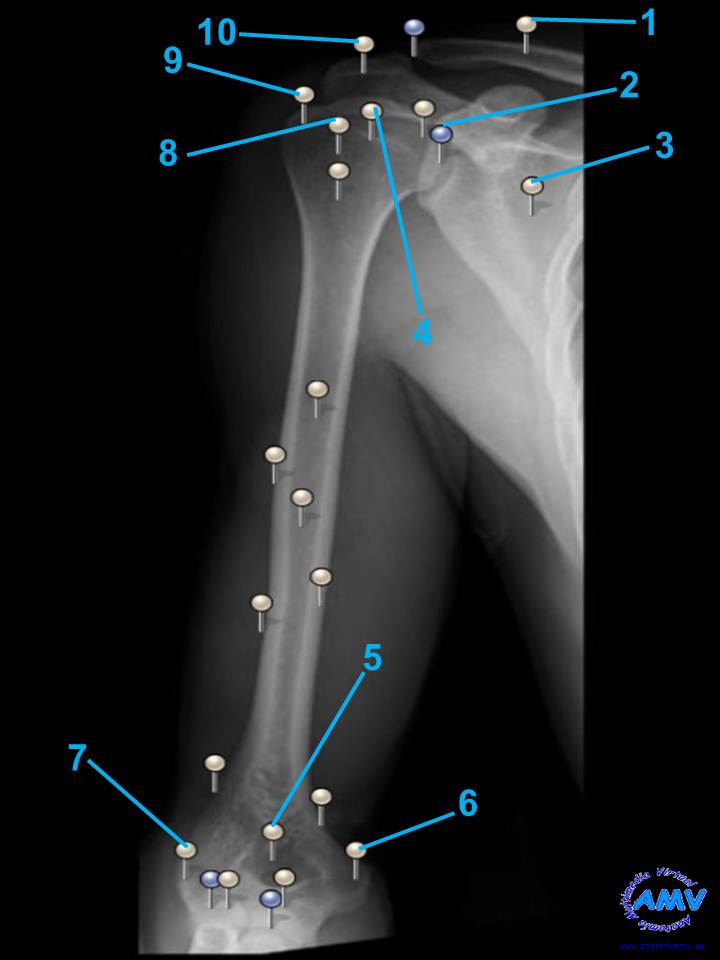

Radiografía del Brazo I

rx_ms_05.jpgIndique que estructura se señala con el número correspondiente:

El nº 1 señala .

El nº 2 señala .

El nº 3 señala .

El nº 4 señala .

El nº 5 señala .

El nº 6 señala .

El nº 7 señala .

El nº 8 señala .

El nº 9 señala .

El nº 10 señala .